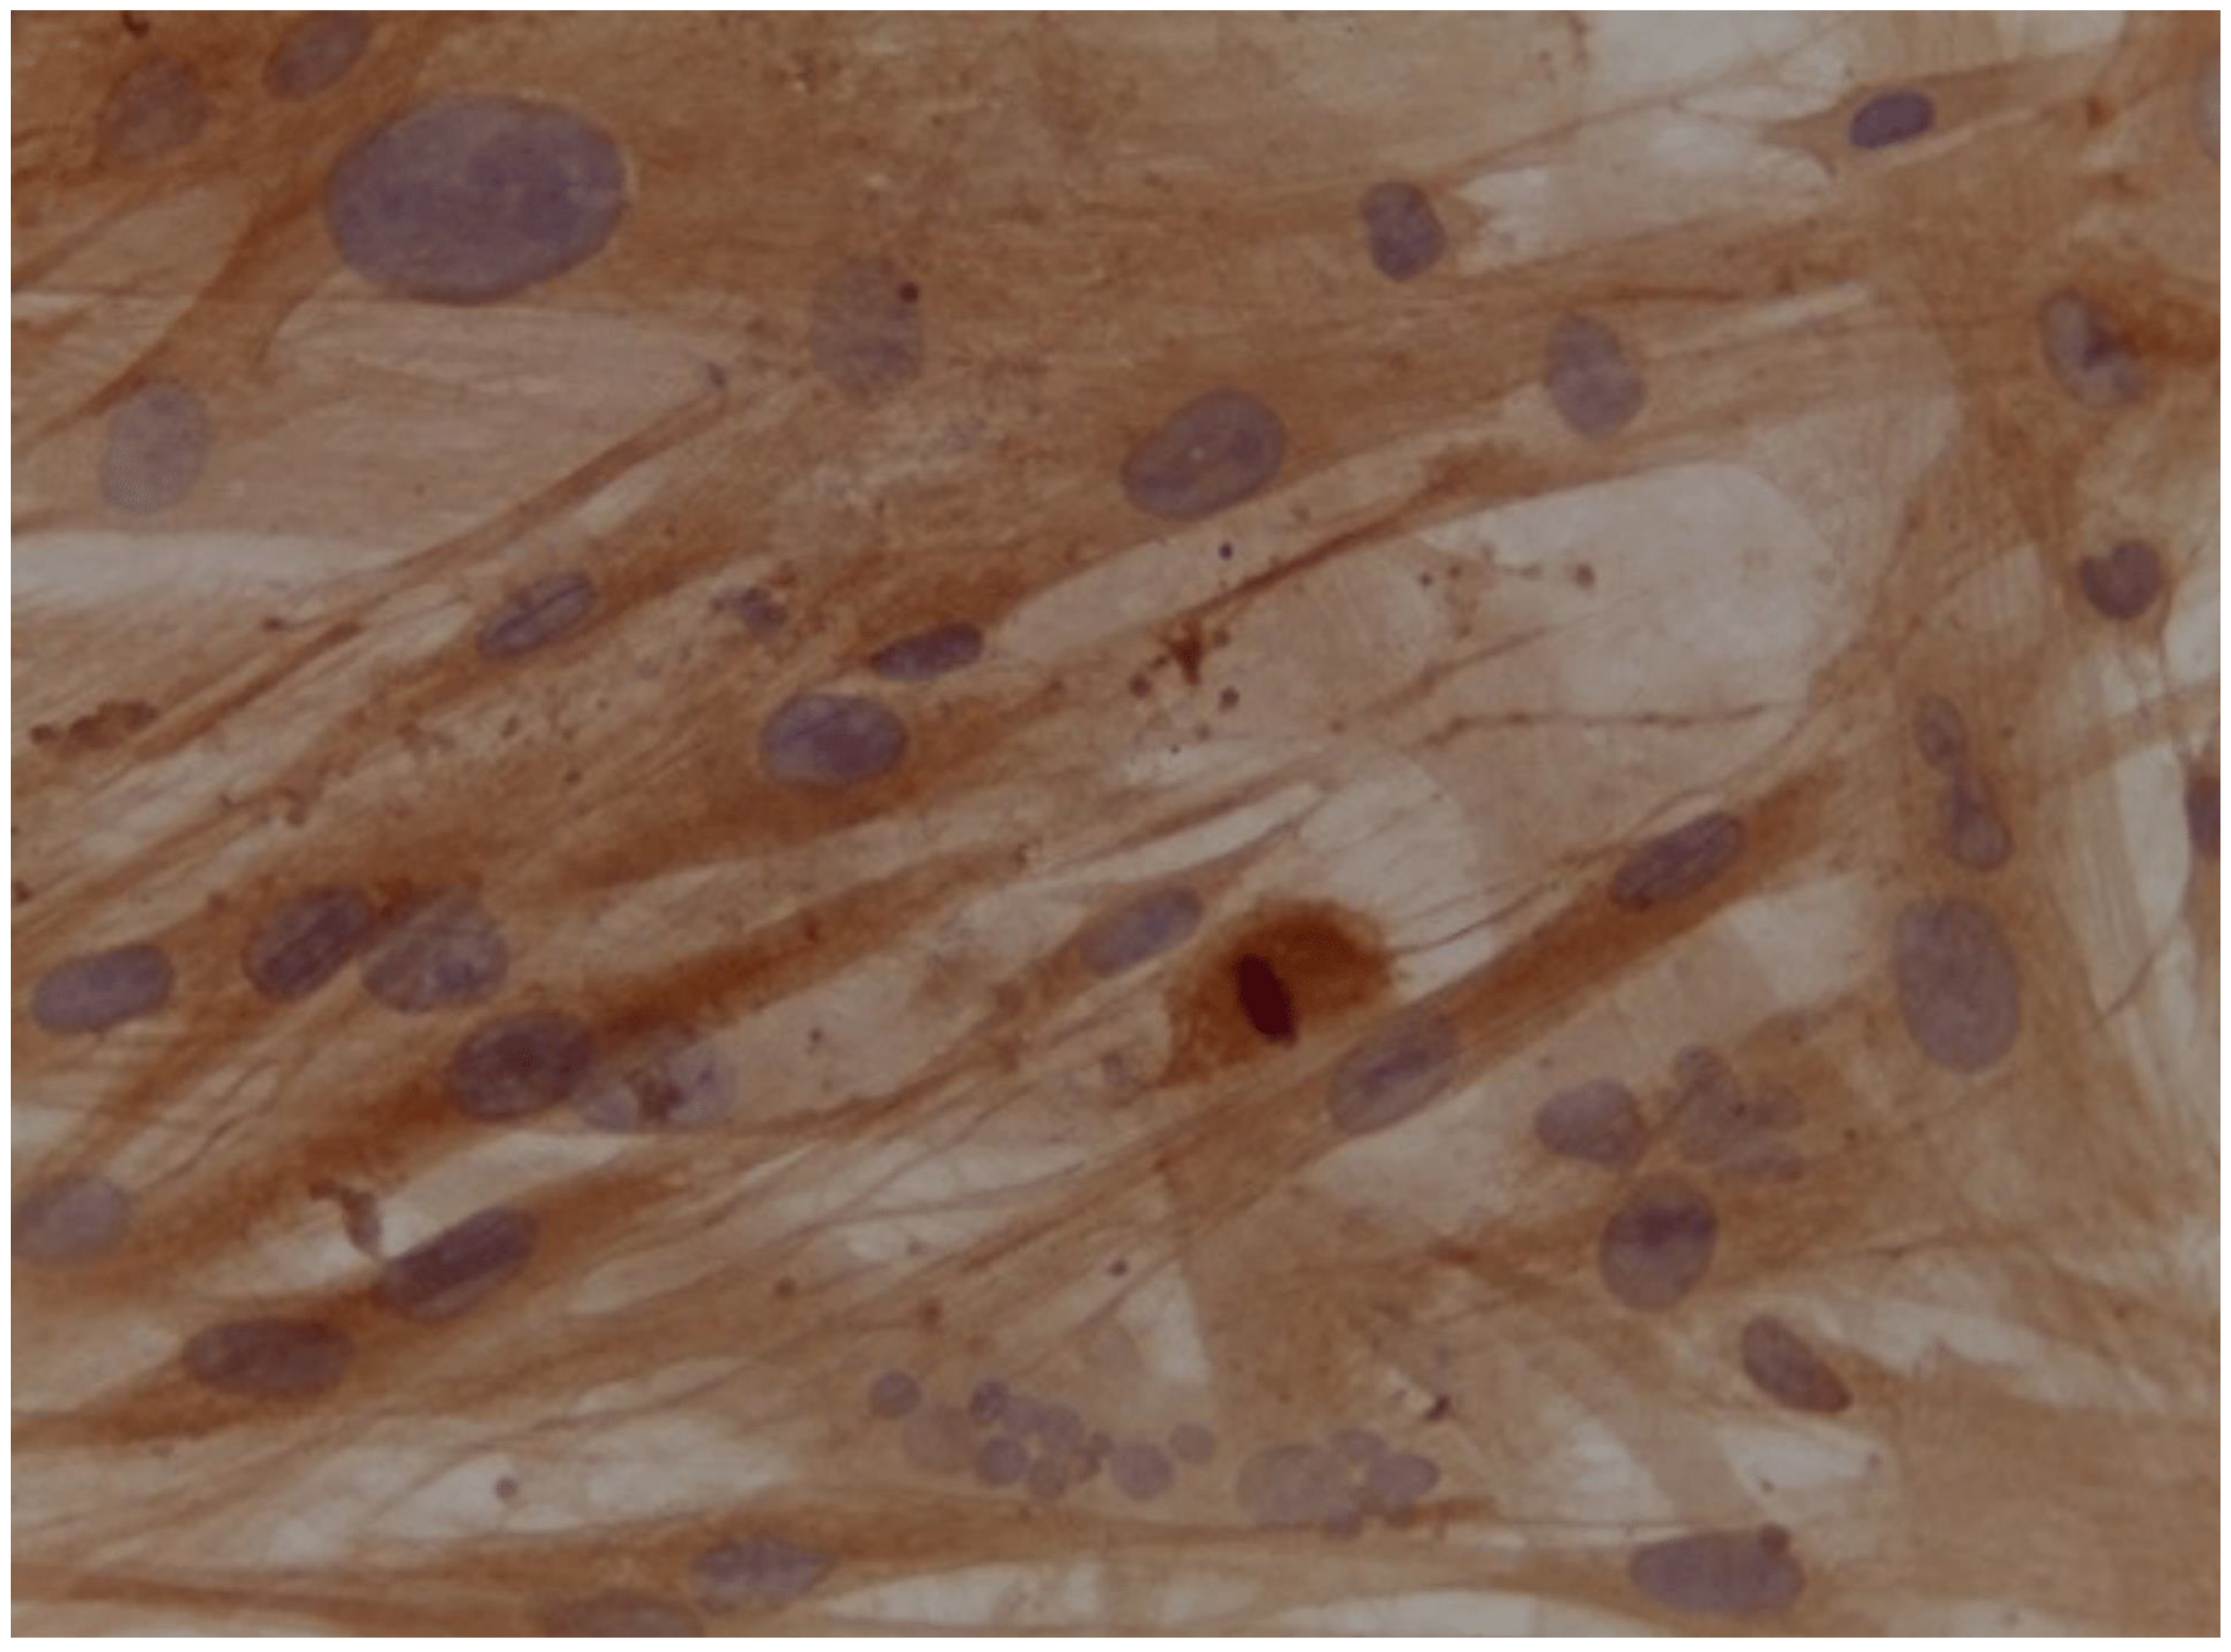

Assessment of expression of cardiomyocyte-like cells differentiation marker Troponin by Immunocytochemistry